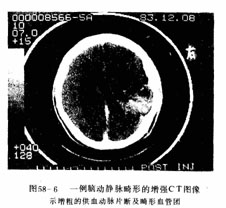

(一)头颅CT扫描 未出血的病例可见有不规则的低密度区,代表AVM周围脑的缺血及退行性变,或因过去曾有出血所形成的脑腔隙。造影剂增强以后可看到密度增高畸形血管团及其增粗的供血动脉及引流静脉(图58-6)。